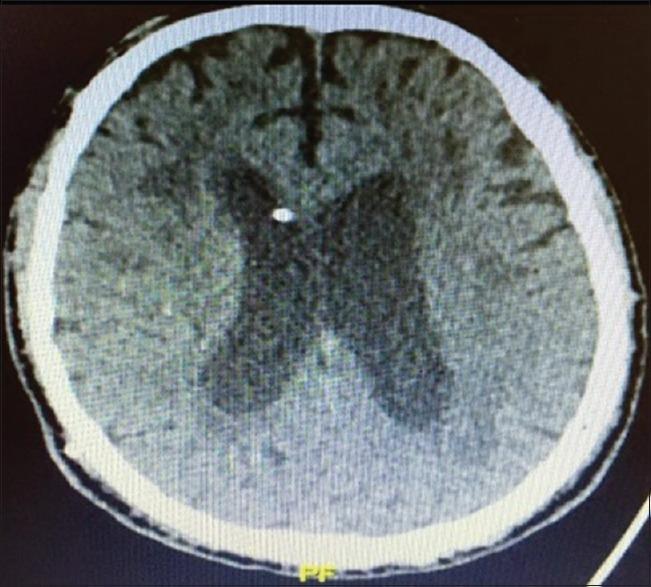

Ventriculoperitoneal (VP) shunt is a day-to-day procedure performed by a neurosurgeon. The most frequent associated complications are obstructive and infectious. Although rare, there are well-reported complications related to the poor positioning of the distal catheter, with perforation of organs and tissues. Still rarer are the complications related to the migration of this catheter.

We describe an atypical case of VP shunt postoperative by normal pressure hydrocephalus. After well-documented proper positioning of the distal catheter into the intraperitoneal cavity, it protruded into the subcutaneous space. Even on a new documented satisfactory abdominal tomography, this catheter migrated back again to the subcutaneous tissue.